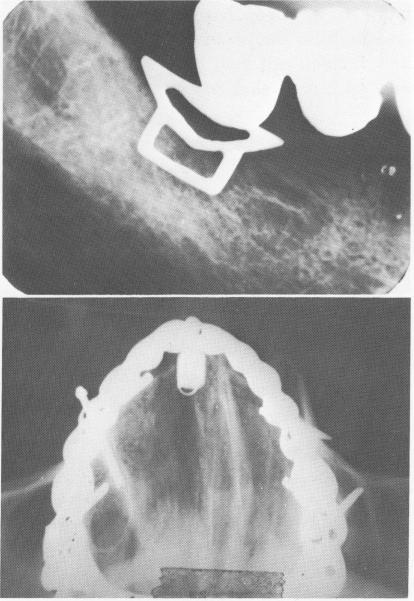

Fig. 14-2. The typical V-shaped breakdown of bone associated with soft tissue invagination is exemplified by this case.

Fig. 14-3. A, Bone resorption also occurs when the shoulder of the blade implant is not buried below the alveolar crest of bone. B, A cross-sectional x-ray reveals perforation of the labial and buccal plates of bone with pin implants, which often can occur. (From Linkow, L. I.: The era of endosseous implants, J. D. C. Dent. Soc. 42 [2] :14-19, 1967.)

A

B